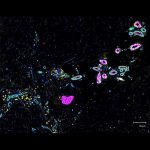

- IBEX uses antibodies so that HuBMAP researchers like Dr. Andrea Radtke at Germain lab can see cellular differences between healthy and tumor cells in lymph nodes. This is an image of follicular lymphoma lymph node showing stromal remodeling, a-SMA (orange) and SPARC (cyan), around B cell follicles (purple). a-SMA (orange) labels fibroblasts, CD20 (purple) labels B cells, SPARC (cyan) labels macrophages, stroma, matrix interactions.